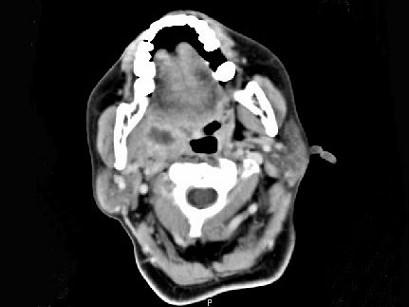

问题 女,52岁,咽喉部疼痛半个月,伴低热,CT如图所示,可能诊断为 ( )

选项 A、咽旁淋巴瘤 B、咽旁转移癌 C、咽部神经鞘瘤 D、鼻咽血管纤维瘤 E、咽旁脓肿

答案 E